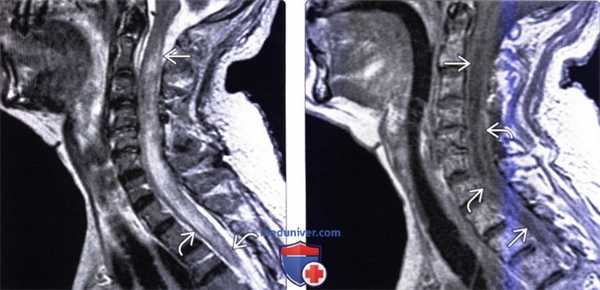

(Слева) Аксиальный срез, T2*GRE МР-И: многокамерное экстрадуральное кистозное образование. Образование через правое межпозвонковое отверстие проникает в эпидуральное пространство.

(Справа) Сагиттальный срез, Т1-ВИ: эхинококковое кистозное образование, поражающее тела и задние элементы нескольких позвонков, но сохранением целостности межпозвонковых дисков. Минимальные реактивные изменения костной ткани обусловливают формирование вокруг кист тонких стенок. Кисты, прорастая кость, разрушают губчатую костную ткань.